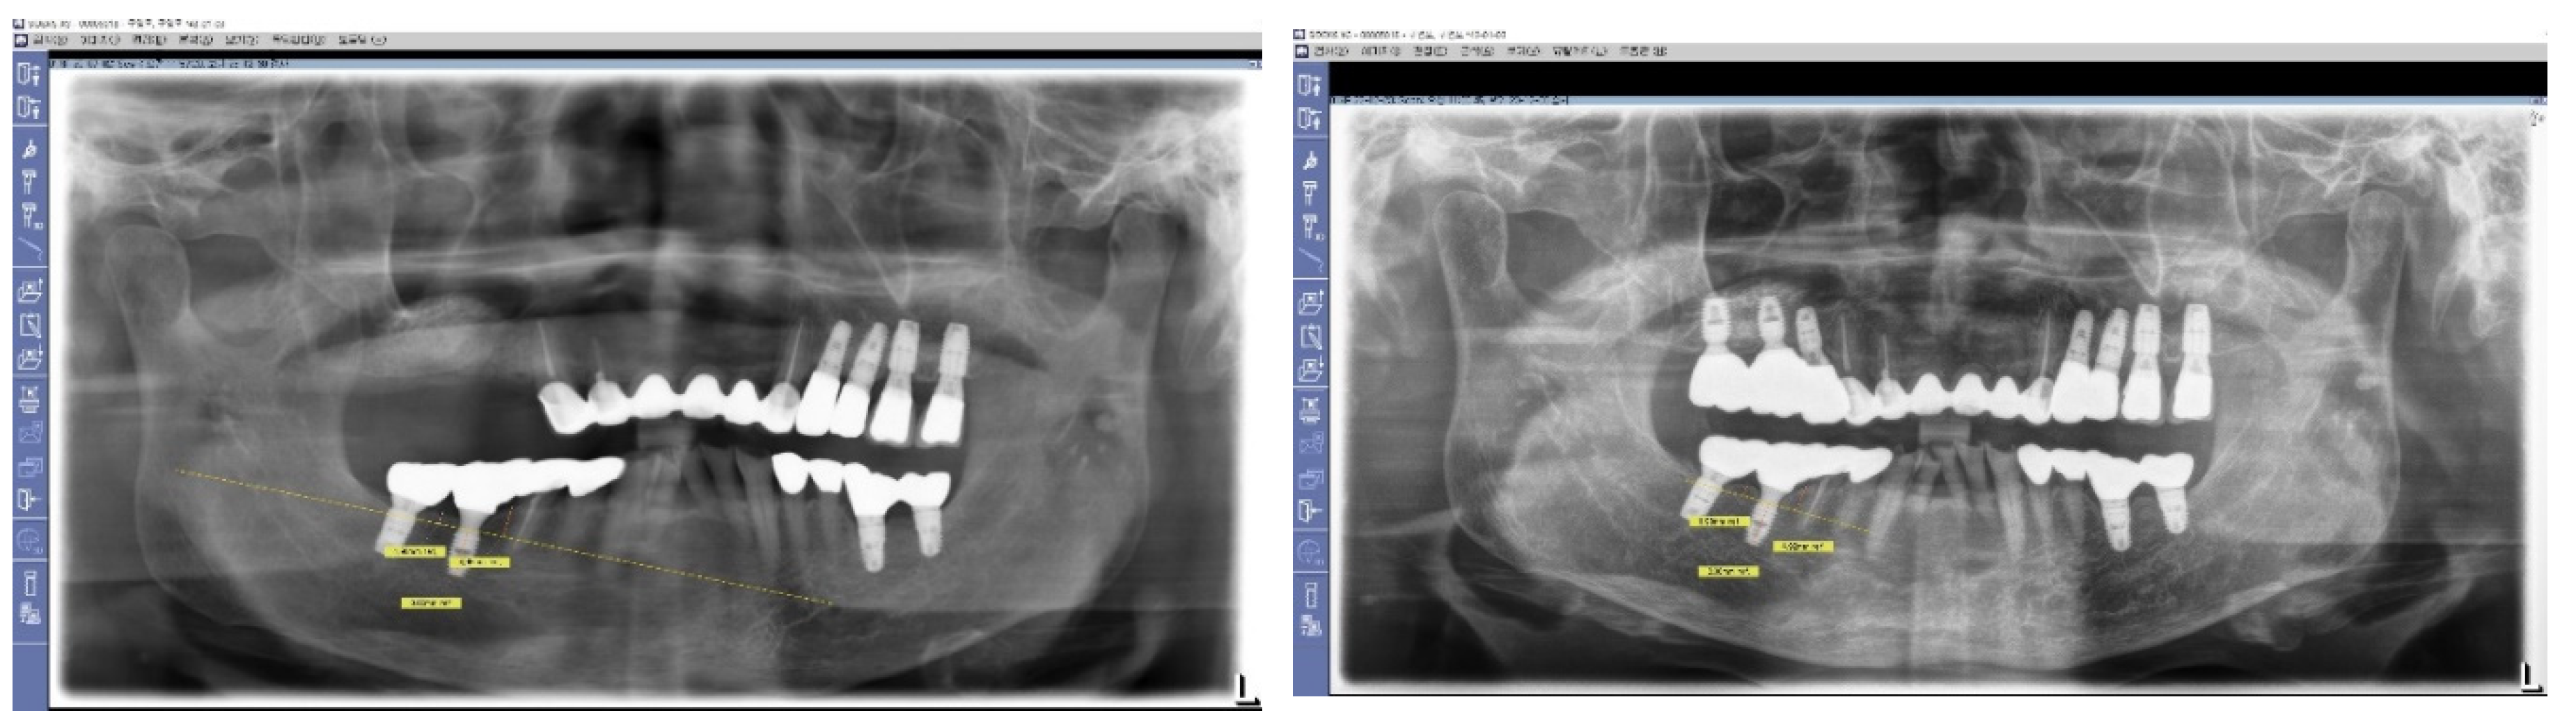

Figure 7. Long-Term Stability of Lower First Implants. This figure displays a panoramic view X-ray taken in 2023, showing the stable results of both lower first implants that were placed in 2012. These implants, which utilize Subcrestally Placed Implants (SPI) with Internal Platform Switching (IPS) design (specifically Bicon implants), demonstrate long-term stability and successful integration.

Results

1.

The crestal bone changes by the measurements of pPD (from panoramic view X ray)

Time of Initial X ray Time of F/U X ray change F/U duration

pPD pPD pPD

Average M 3.8 3.9 0.05 3.3 years

D 2.8 2.8 0.08

2.

The depth of placement (from the 3DSTA)

The depth of placement at the central area The depth of placement at the peripheral area

cPD/M cPD/D cPD/B cPD/L average deepest cPD pPD/M pPD/D pPD/B pPD/L average Deepest pPD

mean 1.9 1.6 1.8 1.7 1.7 2.3 3.7 2.9 2.0 2.3 2.7 4.0